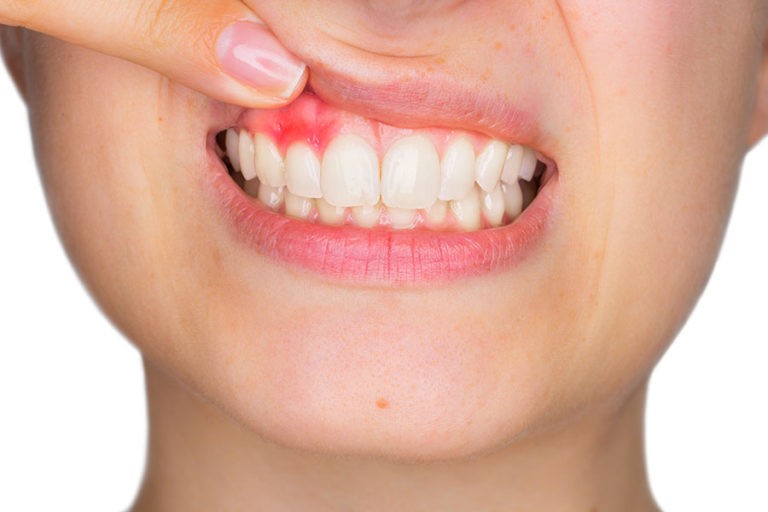

La gengivite e la parodontite sono malattie delle gengive e dei tessuti che circondano e supportano i denti e sono causate dai batteri contenuti nella placca e nel tartaro.

Una donna in dolce attesa è maggiormente predisposta ad avere gengive infiammate e sanguinanti a causa dei cambiamenti ormonali.